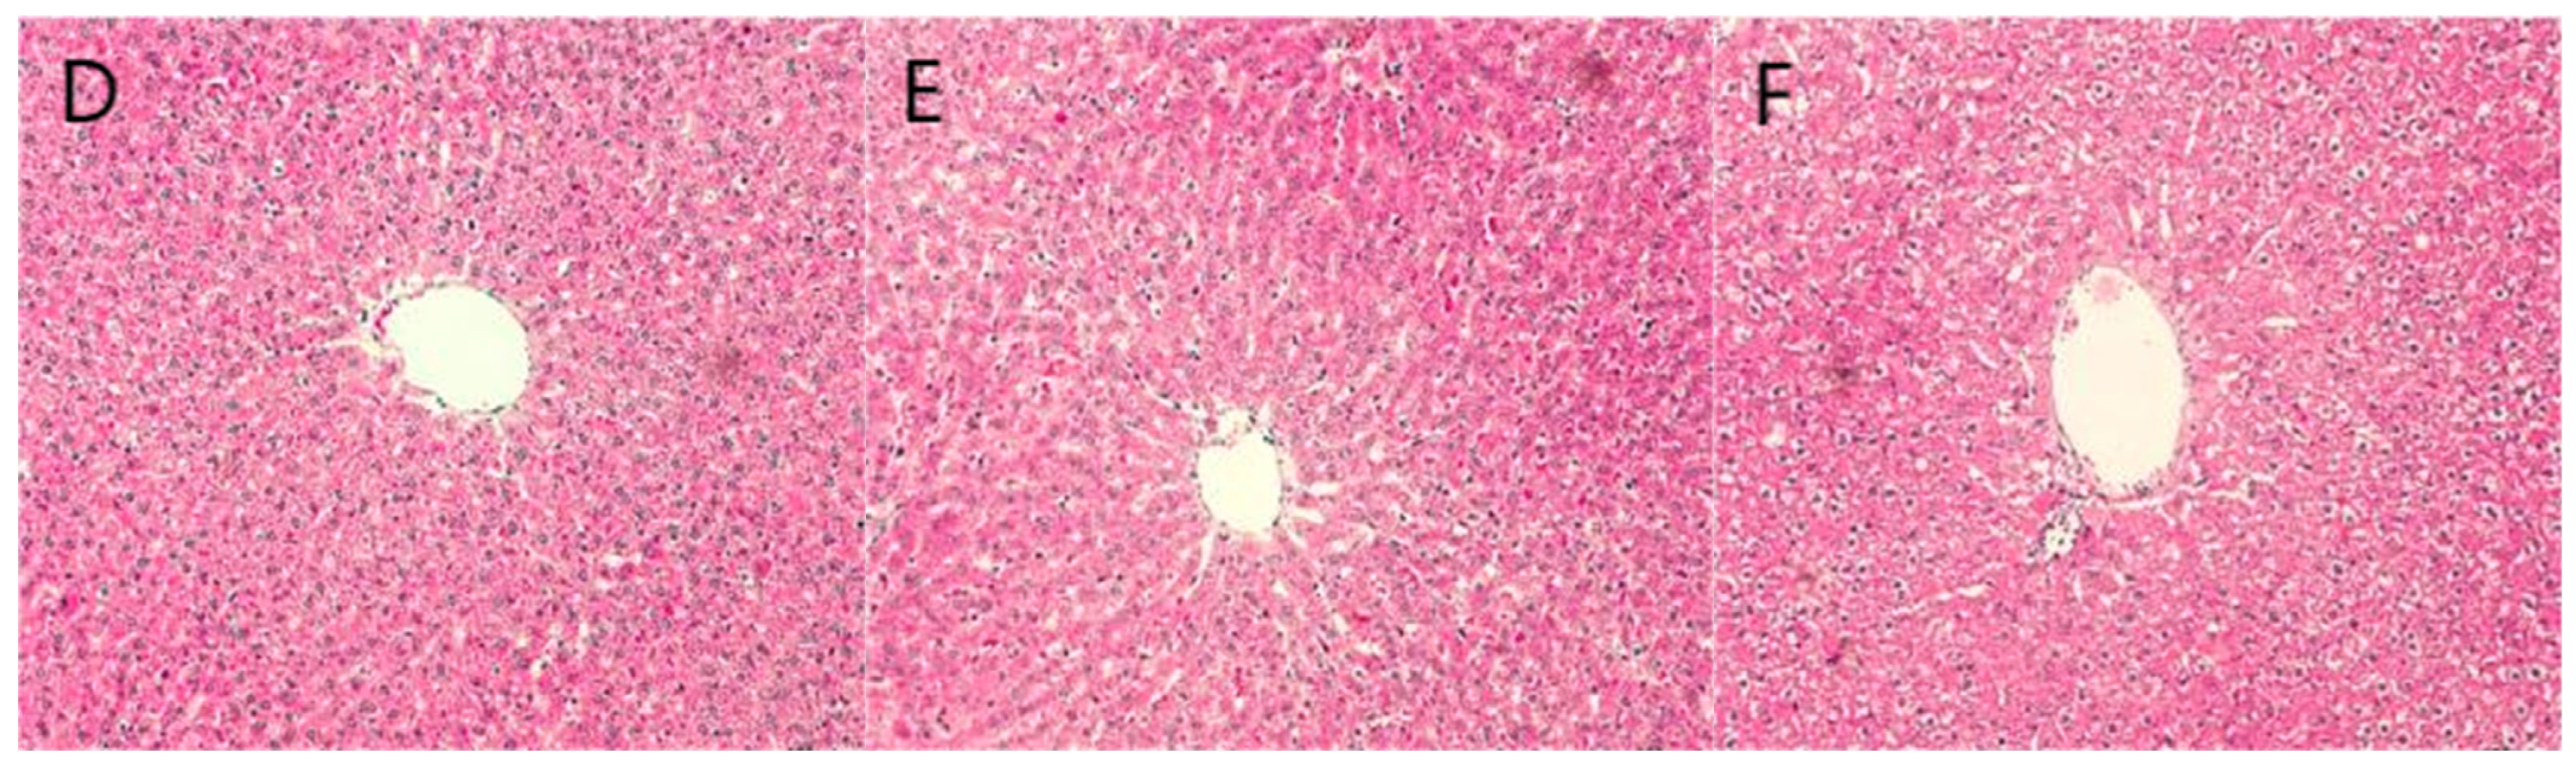

2.6. Staining Results

3.2. Animal Experimentation

4.8. Tissue Embedding Sectioning and Staining